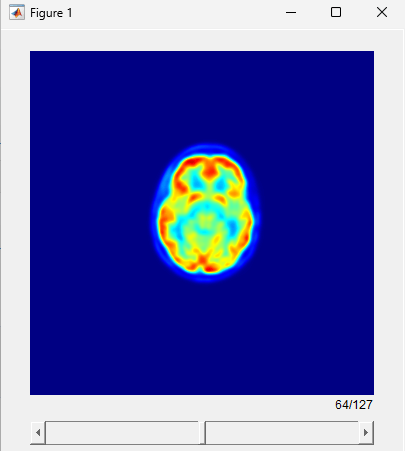

Visualize the static PET volume.

figure sliceViewer(staticPET,Colormap=jet(256))